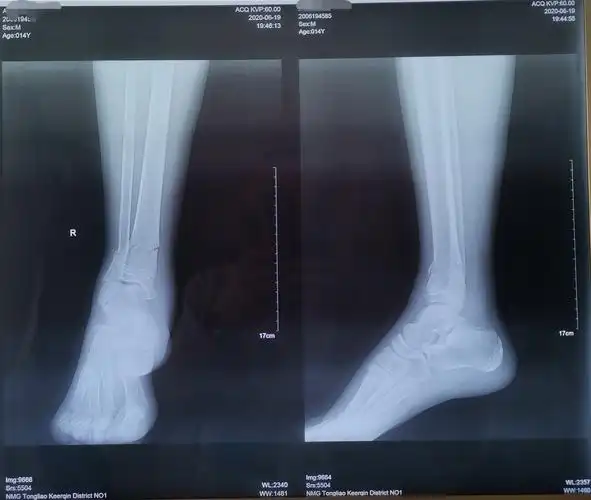

医生您好,我小腿腓骨骨折,没错位,没打石膏,没手术,也没做任何固定

右小腿骨折

右小腿腓骨骨裂,目前只用石膏固定,有两个星期了,什么时间可以拆除

腿部胫骨骨折x线照片

9岁小孩左小腿胫骨中下段青枝骨折要不要固定,谢谢了